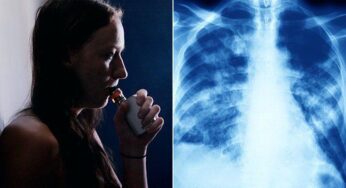

The Effects of Vaping on Your Lungs

Vaping, also known as e-cigarettes, is increasingly becoming popular among young adults. What contributes to the popularity of vaping is…